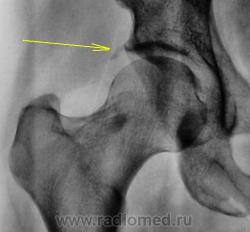

Пациентка в течение года предъявляет жалобы на боли в тазобедренном суставе. Направлена врачом хирургом в рентгеновский кабинет для рентгенографии тазобедренного сустава. Произведена рентгенография в прямой стандартной проекции.

Признаки не выраженного коксоартроза есть, а участок уплотнения в шейке бедренной кости-остеопойкелии.

Артроз и эностоз в шейке

А как быть с истончением кортикального слоя и умеренной деформацией кости по медиальному контуру.

Конечно, была проведена рентгенография для сравнения, но там все нормально, также нет, помеченного стрелочкой.

Если честно то это интересно. Тут нету основного компонента деформирующего остеоартроза - сужения суставной щели. Зато как указал Катенев есть другие изменения... хммм...

По большому счету, "рентгенологически", речь о деформирующем артрозе не шла. Хирургом в направлении написан "формальный диагноз".